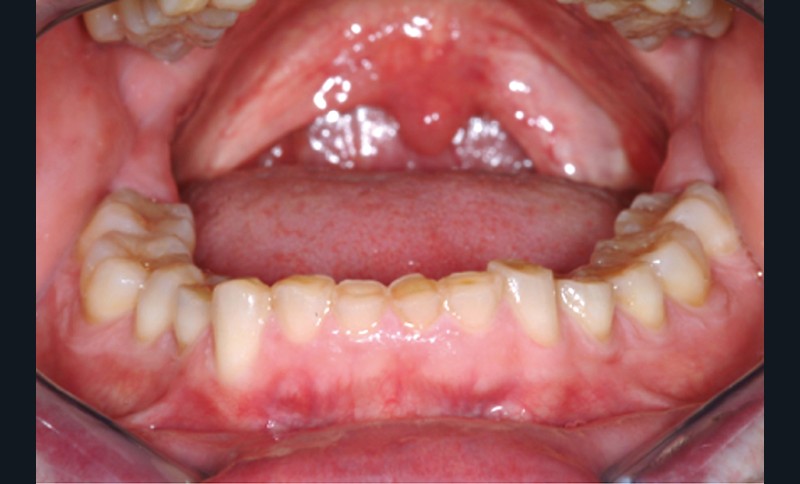

Jean-Pierre Attal : Exactement, car il est possible d’appliquer le protocole de la technique « 3 steps » aux patients présentant des pertes de substance d’origine attritive (bruxisme) (fig. 5).

Pour autant, Francesca Vailati exposera les précautions particulières à prendre dans ce contexte dysfonctionnel. Le principe du traitement est de protéger rapidement la dentine par collage (uniquement des restaurations par addition afin de ne pas délabrer davantage les dents déjà altérées) et de permettre ainsi au patient de dégrader les restaurations plutôt que l’organe dentaire.